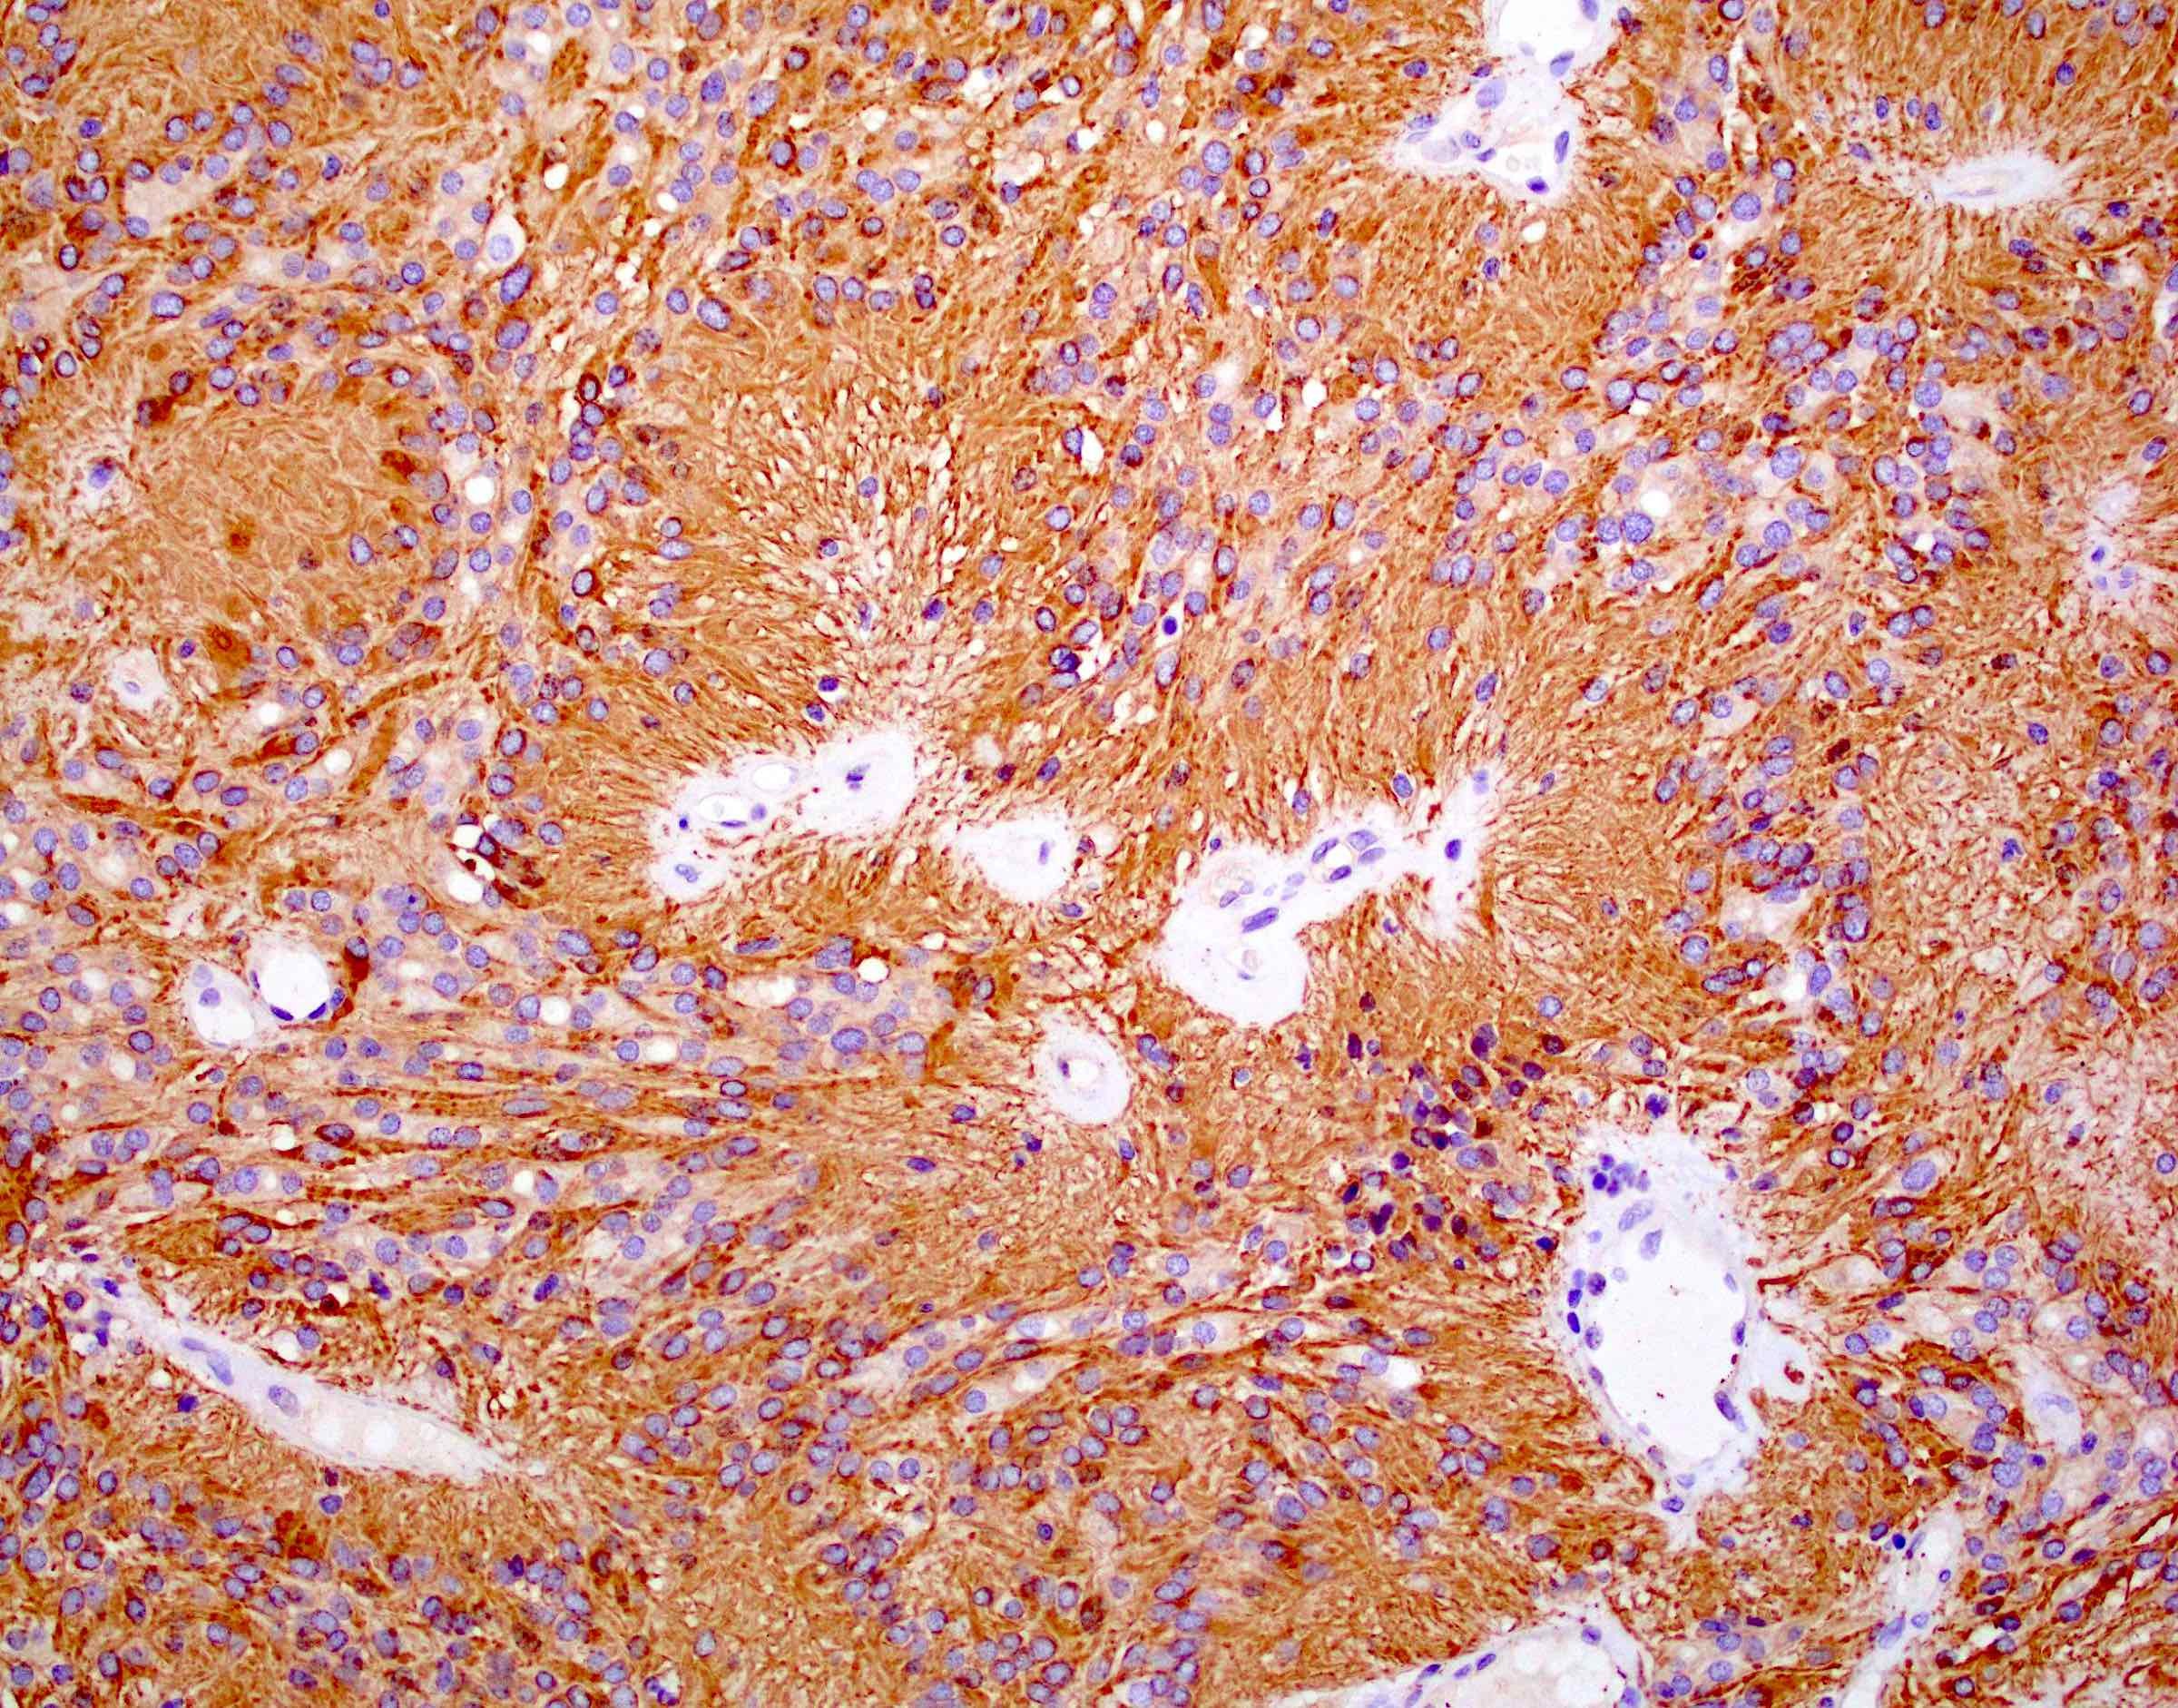

Microscopic (histologic) images

Positive stains

- Positive for S100, GFAP, vimentin

- Perinuclear dot-like pattern of EMA and D2-40 staining

- CD56 staining in lumina and tumor cells

- Variable membranous or dot-like staining for CD99

- Can have focal staining for keratin (CAM 5.2) and synaptophysin

- L1CAM can be positive in some supratentorial ependymomas but mostly is seen in RELA fusion tumors (Am J Surg Pathol 2019;43:56)

- In posterior fossa ependymomas, decreased expression of H3K27me3 is seen in posterior fossa group A, which has a worse prognosis (Acta Neuropathol 2017;134:705)